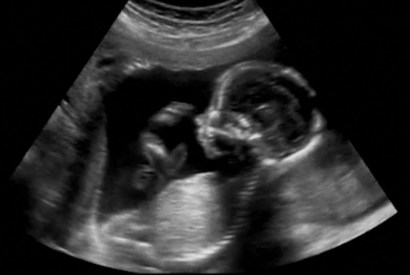

Silencing dissent over abortion

Well-informed Flat White readers will be aware of the two abortion bills before the NSW Parliament, and the remarkable petitioning effort against it…

It’s a liver!

A US scandal has abortion doctors offering a macabre menu of baby body parts